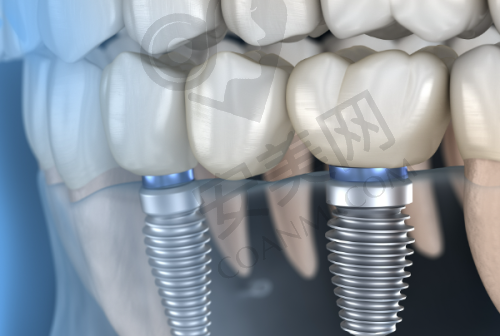

韩国维钛种植牙是一款在种植牙市场上备受关注的产品。它采用了精良的钛合金材料,这种材料具有良好的生物相容性,能够与人体牙槽骨更好地结合,提高种植牙的稳定性和成功几率。韩国维钛种植牙的表面经过特殊处理,能够促进骨细胞的生长和附着,加快种植牙与牙槽骨的愈合过程。此外,该种植牙的设计符合人体口腔生理结构,能够更好地修复牙齿的咀嚼功能和美观度。它的外观与真牙相似,几乎可以达到以假乱真的成效,让患者在修复口腔功能的同时,也能拥有自信的笑容。